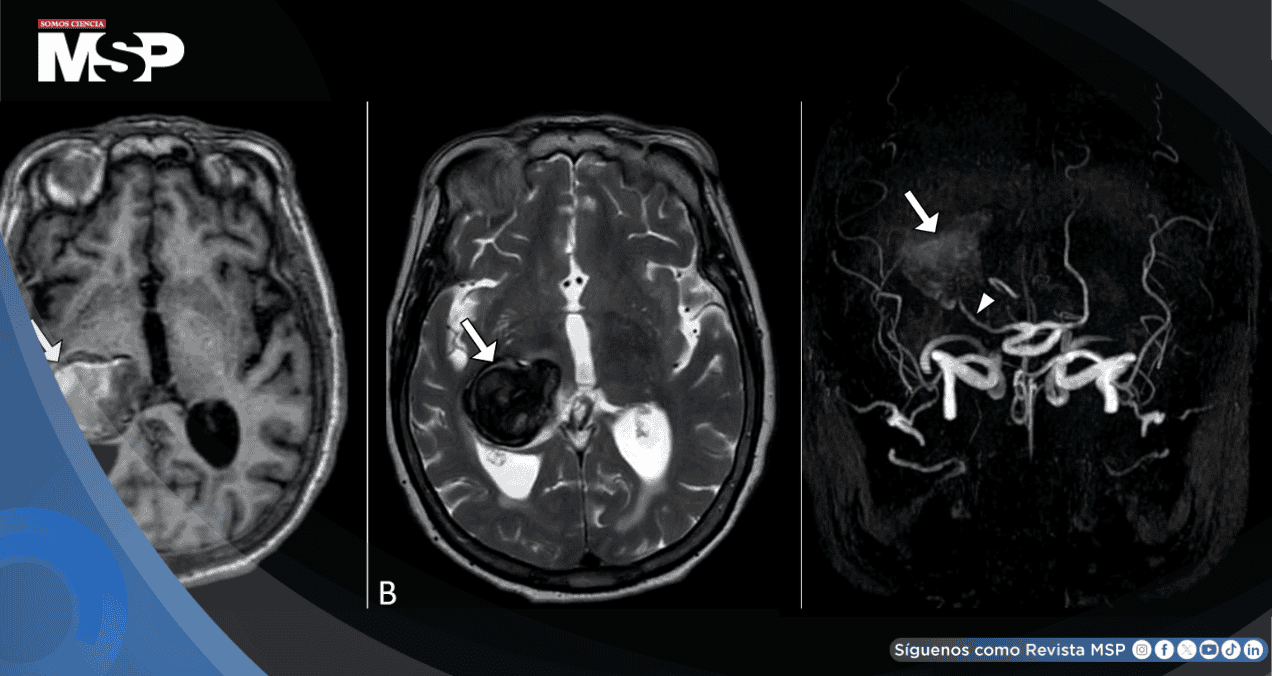

Los análisis de sangre no mostraron signos de infección o inflamación, lo que descartaba otras causas. El diagnóstico llegó con una resonancia magnética cerebral, que mostró una dilatación anormal y gigante en la arteria cerebral posterior derecha, confirmándose que se trataba de un aneurisma.

Los aneurismas en esta arteria en particular son bastante raros, siendo solo alrededor del 1% de todos los aneurismas intracraneales. Sin embargo, tienen una característica que los hace especialmente relevantes: tienden a ser de gran tamaño.

La arteria cerebral posterior es una carretera principal que suministra sangre a áreas vitales del cerebro responsables de la visión, como el lóbulo occipital. Cuando un aneurisma se forma y crece en esta zona, puede presionar las estructuras circundantes, lo que explica por qué este paciente sufría de alteraciones visuales tan específicas.